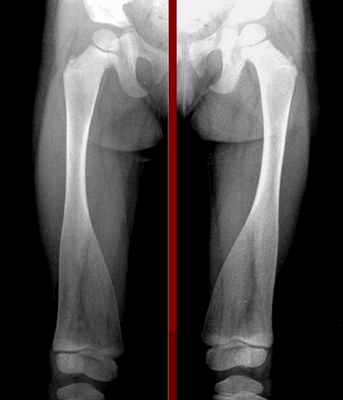

Характерным признаком заболевания является сильное смещение трубчатых костей при одновременном и значительном расширении колбы Эрленмейера в ногах. Особенно симптомы выражены при поражении бедренной части. При метафизарной дисплазии негативные изменения в строении черепа минимальны. В редких случаях сильно выступают лобные доли над глазницами, создавая асимметричное строение лица.

При диагностике врачи обращают внимание на характерное поражение проксимального отдела шейки бедра. Кости имеют неправильную форму, недостаточную плотность, низкое содержание кальция и микроэлементов. На рентгеновских снимках заметны неровные контуры, расширенные участки эпифизов.

Для пациентов с типом MакКьюзика характерны хроническая анемия, патологии кишечника. На рентгеновских снимках заметно увеличение метафизов в области коленного сустава. В детском возрасте нередко встречается двояковыпуклое строение позвонков, которое постепенно исчезает после взросления.